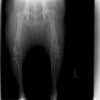

術後側面像

術後正面像

術前に25°であったTPAは、TPLO実施により7°に矯正されました。症例の歩行状態は良好です。